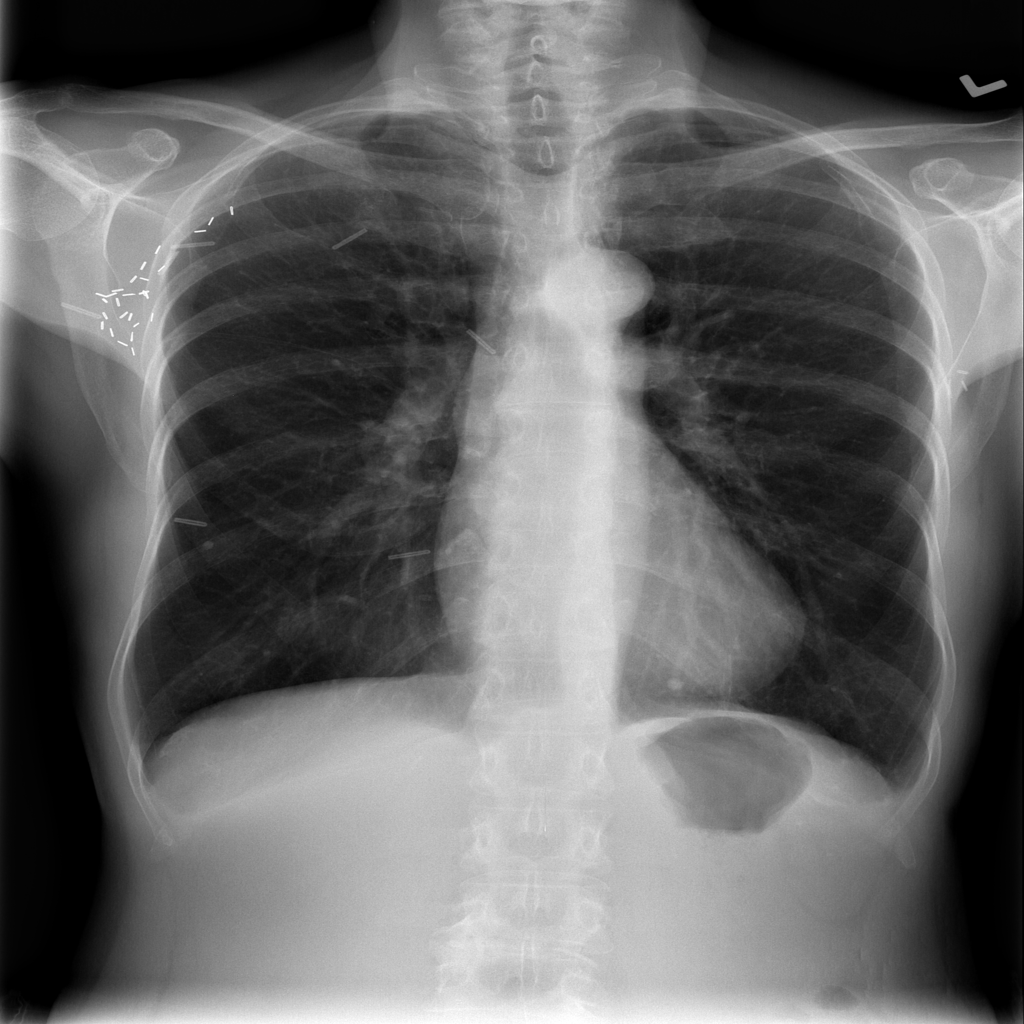

Showing up to 90 reference images for Emphysema.

PAT-C255 · IMG-000Emphysema

PAT-C255 · IMG-000

PA